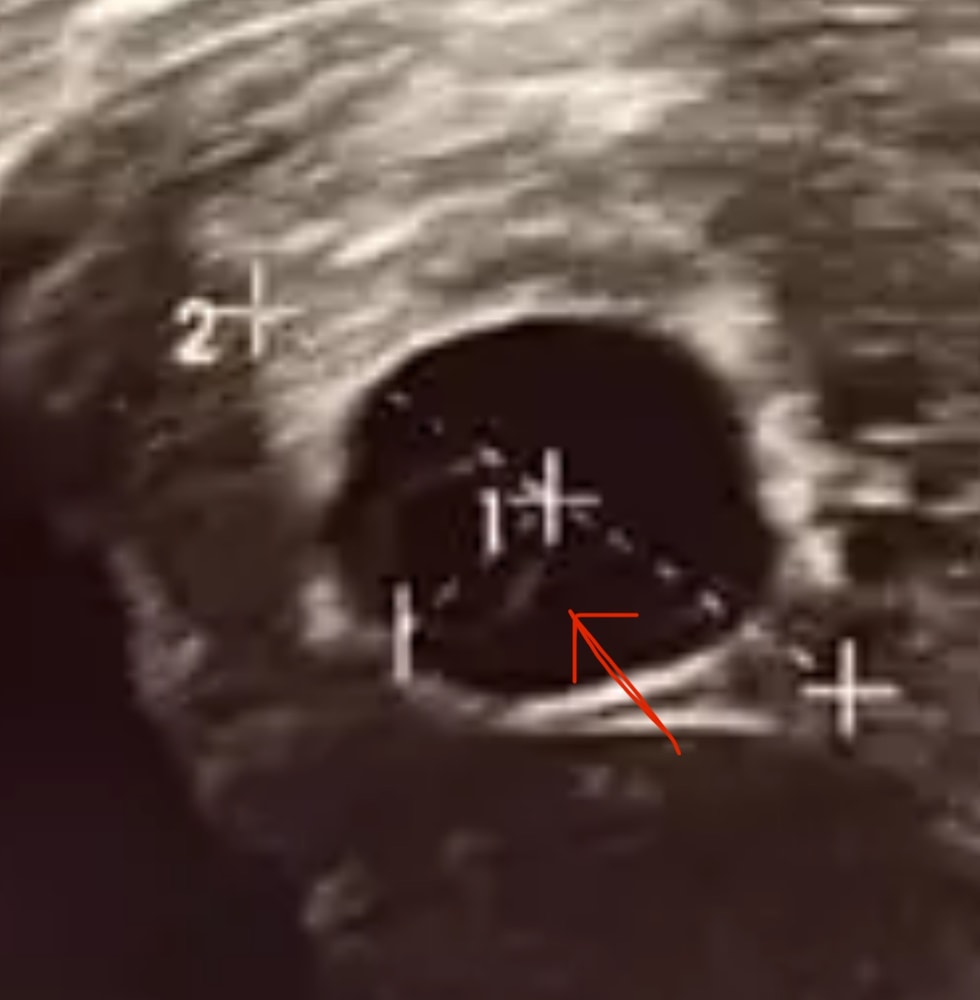

Очень смахивает на зарождение эмбриончика)

Anastasiya, я про уплотнение на ЖМ